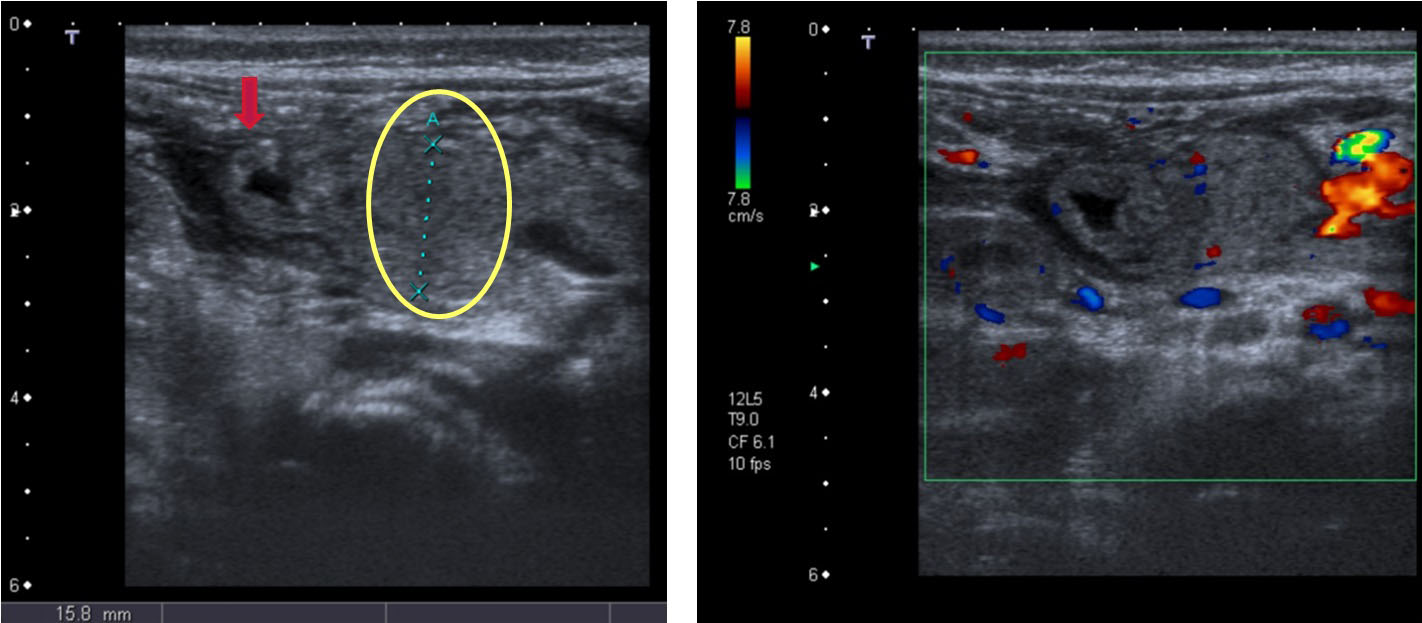

Se identifica un aumento del tamaño del páncreas de forma difusa pero más acentuada en la región de la cabeza pancreática (círculo), que presenta una morfología redondeada y globulosa, con una ecogenicidad discretamente heterogénea y unas medidas aproximadas de 18 × 18 mm. No se identifica dilatación del conducto de Wirsung. También se identifica un engrosamiento parietal difuso del duodeno (flecha) (4,3 mm de espesor).

Existe un aumento de la vascularización de la región pancreático-duodenal y territorios adyacentes en el estudio Doppler, que sugieren un proceso inflamatorio.